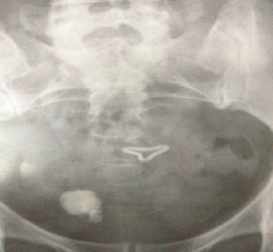

查体:一般生命体征平稳,心肺腹查未见明显异常。 尿常规示:WBC 30~60个/HP,RBC 20~40个/HP。 X片提示:膀胱区见一丝状异物,异物一端见3.5cm *2.0cm 阳性结石影。

术前诊断:膀胱结石,膀胱异物。 予完善相关术前检查,查无明显手术禁忌,予择期行膀胱镜检。,检查中见一金属样异物与膀胱后壁粘连,异物上附满泥沙样结石,尾部包裹一直径约3.5的灰黄色结石,连接钬激光装置粉碎结石后见一变形的节育环,异物钳完整取出节育环及与之相连之尾丝.